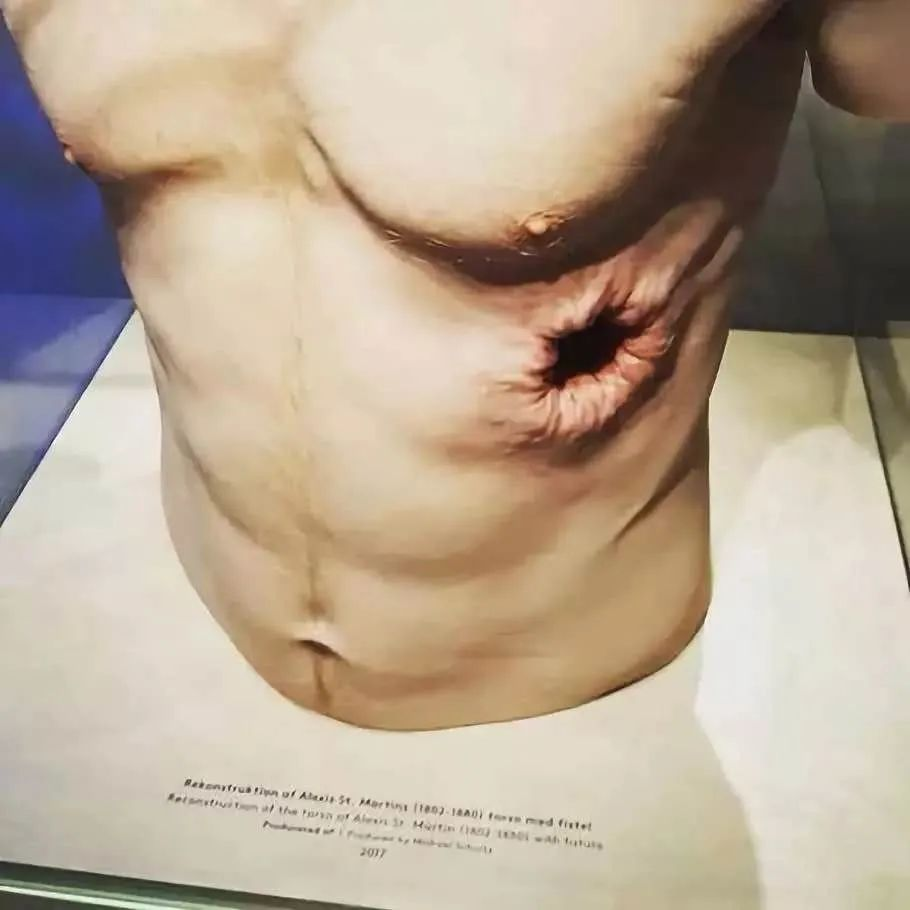

说出来你可能不信,如今人类在医疗上也有类似的胃造瘘术。这源于一位不幸的受伤工人马丁的启发。偶然的一天,这位工人被猎枪近距离射中了胸膛后,打穿了胃。在医生的救治下,他的消化系统神奇地恢复了正常,可他那被打穿的胃却没有办法再完全愈合了。

大约到了十个月后,马丁也形成了一个硬币大小的永久性胃瘘。其胃部的伤口,也和胸腔外面的伤口粘连在一起。在这种情况下,他胃里的内容物可自由地进出体内外,但又不会流到腹腔处腐蚀体腔。

马丁伤口重建的模型

此外,胃酸还能对伤口进行消毒,所以不用缝合也不会发炎。但每次进食时,马丁都只要拿纱布、木塞等物件堵住伤口。而在日常生活中,他也得格外小心,否则一不小心胃液就可能会漏出来。